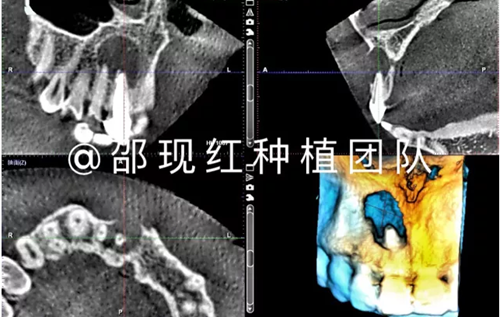

植骨術(shù)后9個月成骨情況